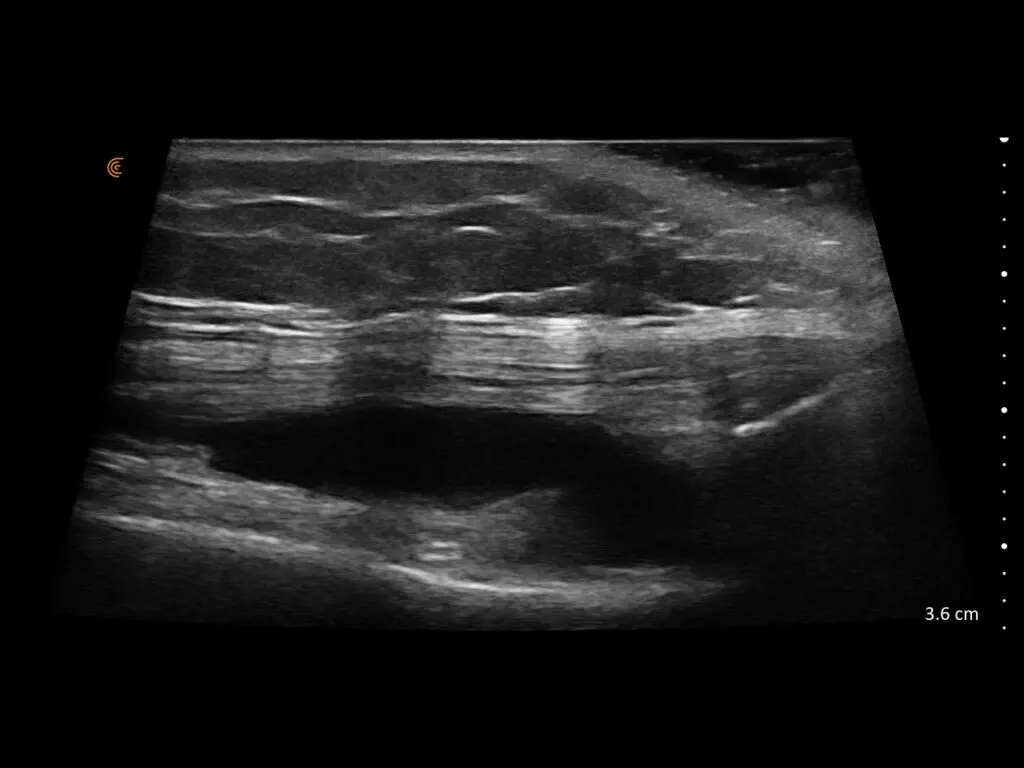

ProbeFix Dynamic is a new device that enables high-quality ultrasound measurements during dynamic exercise by keeping an ultrasound probe in place, allowing for muscle monitoring during intense movement and creating new research possibilities in muscle imaging.